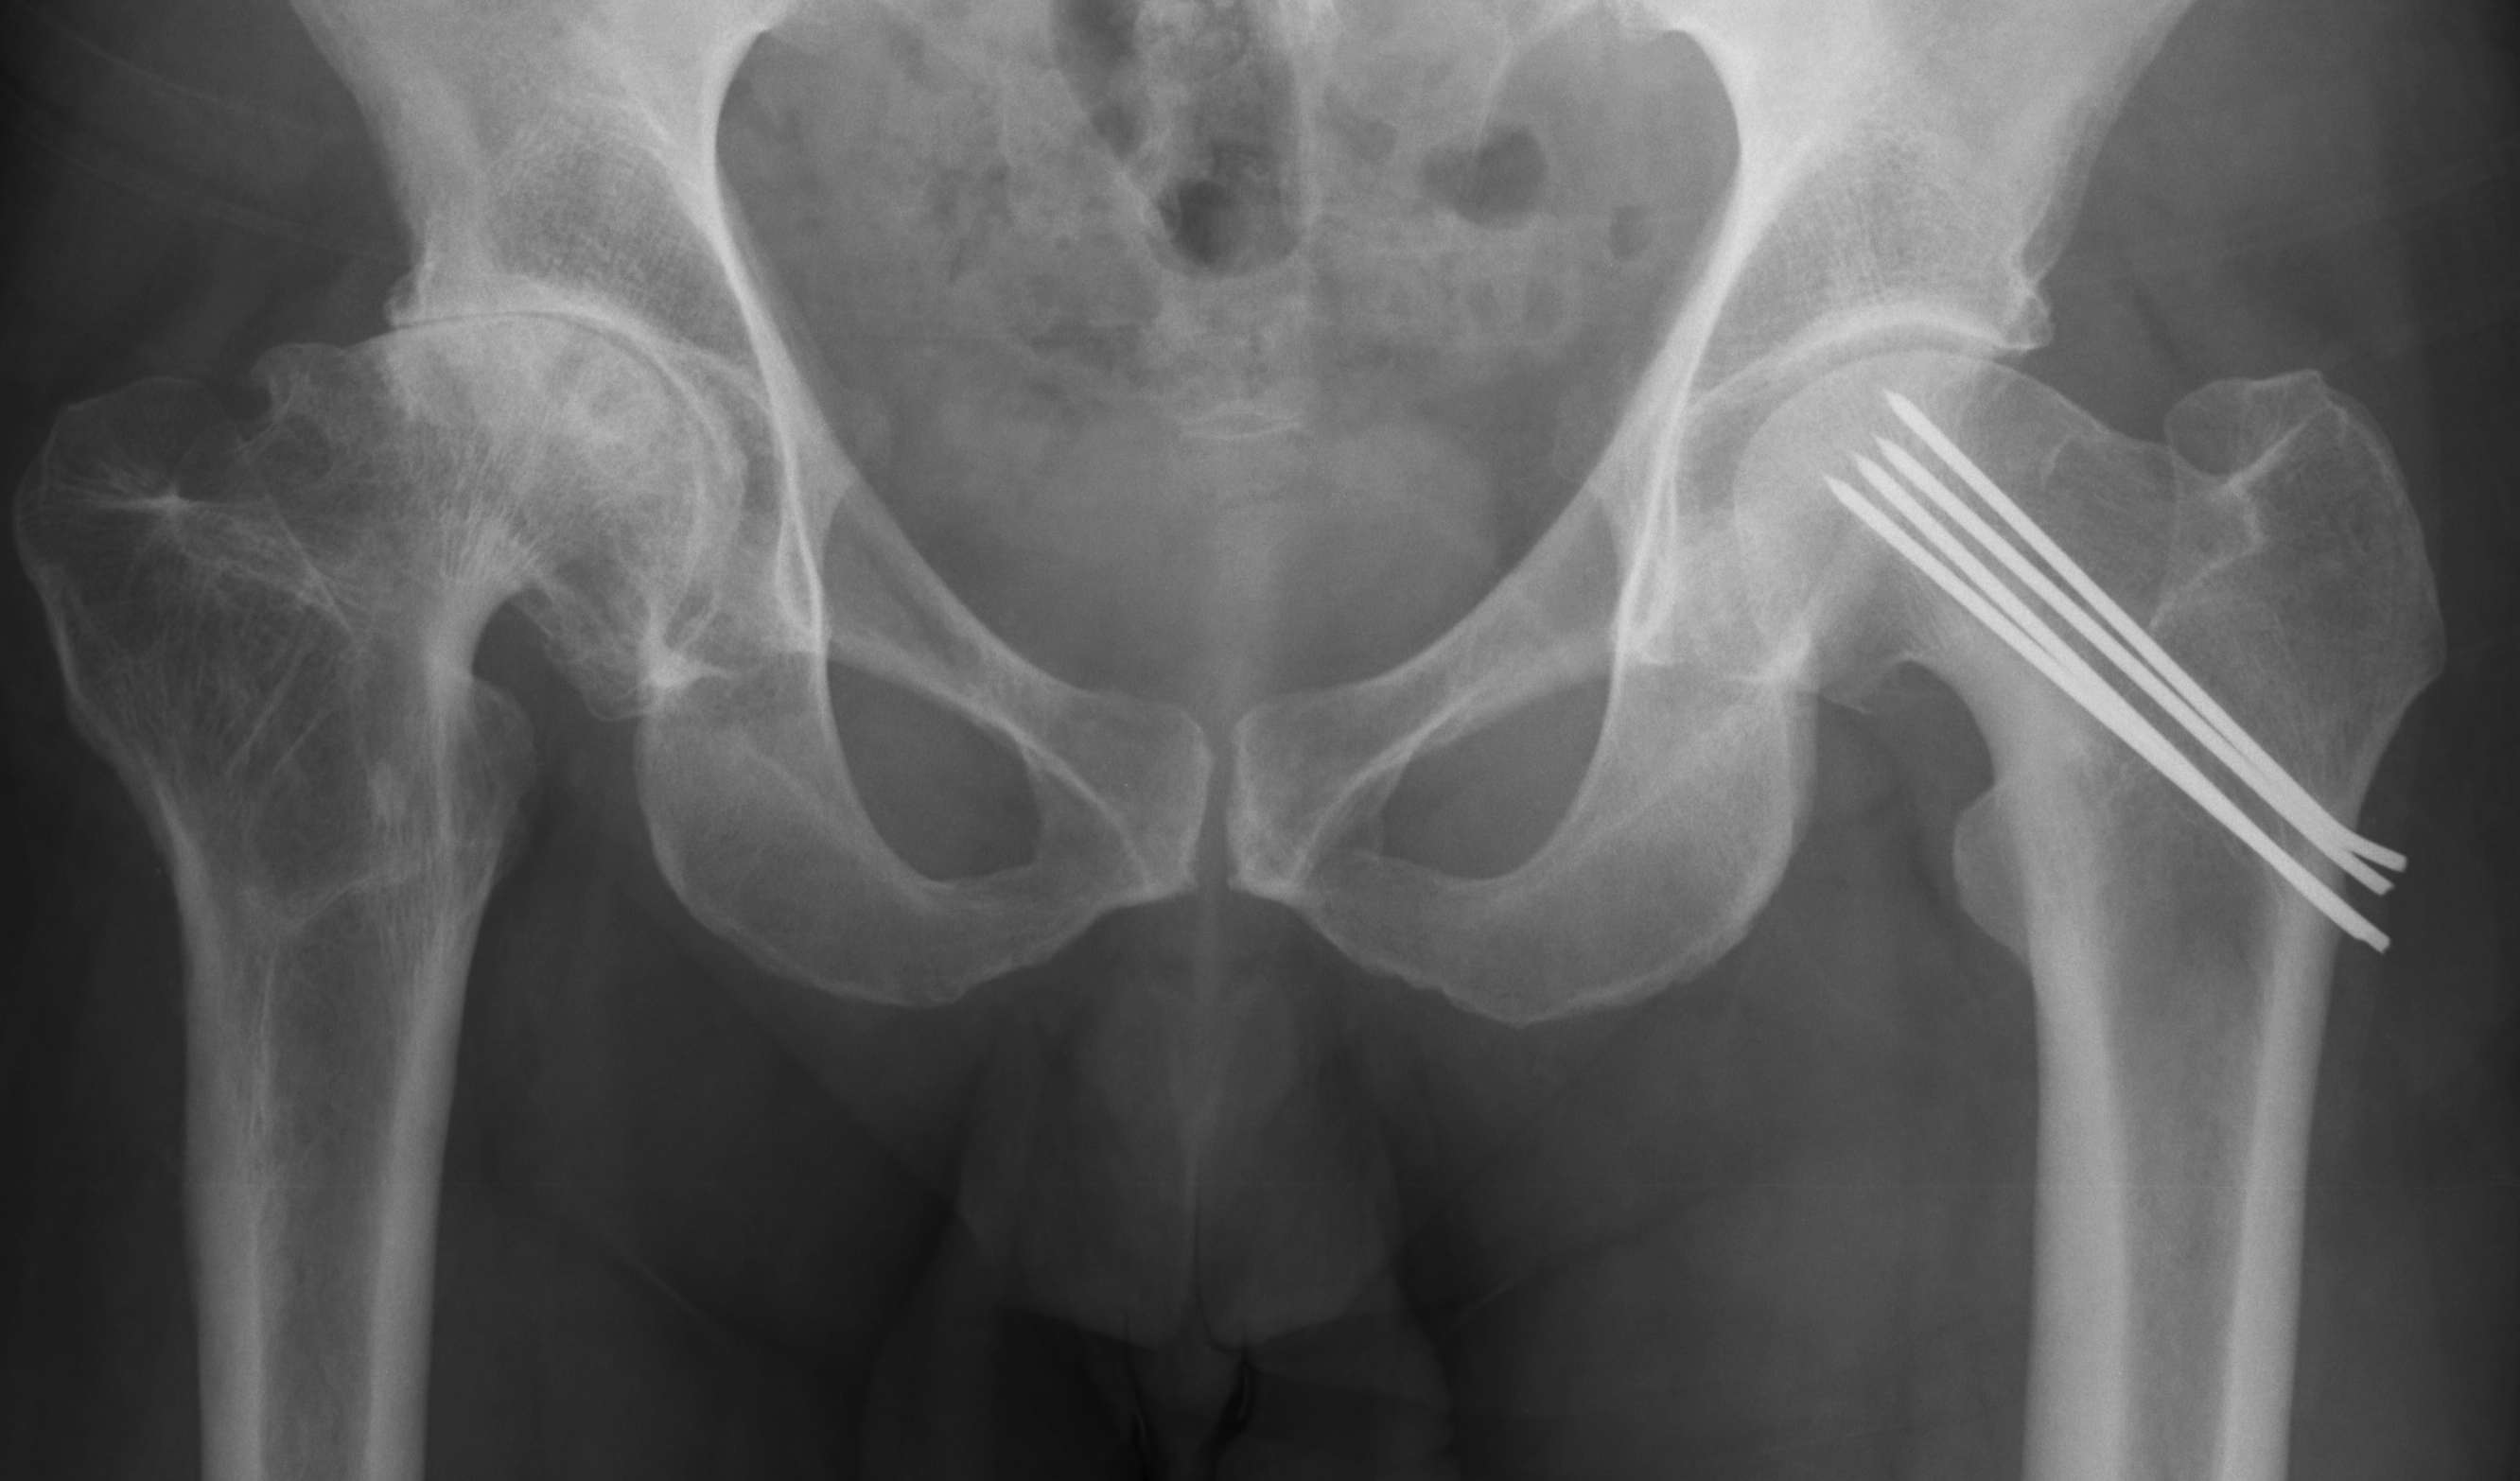

SCFE

Indications for THA

Osteoarthritis

- abnormal morphology

- loss of head neck offset

- bony impingement on acetabulum

AVN

Post traumatic osteoarthris (PTOA)

Indications

< 60 with good bone stock and preserved joint space

Reduction

Union rates increased with anatomical reduction

Options

- closed reduction

- open reduction / if closed reduction fails

Accept

- no varus

- < 15o valgus

- < 10o AP plane